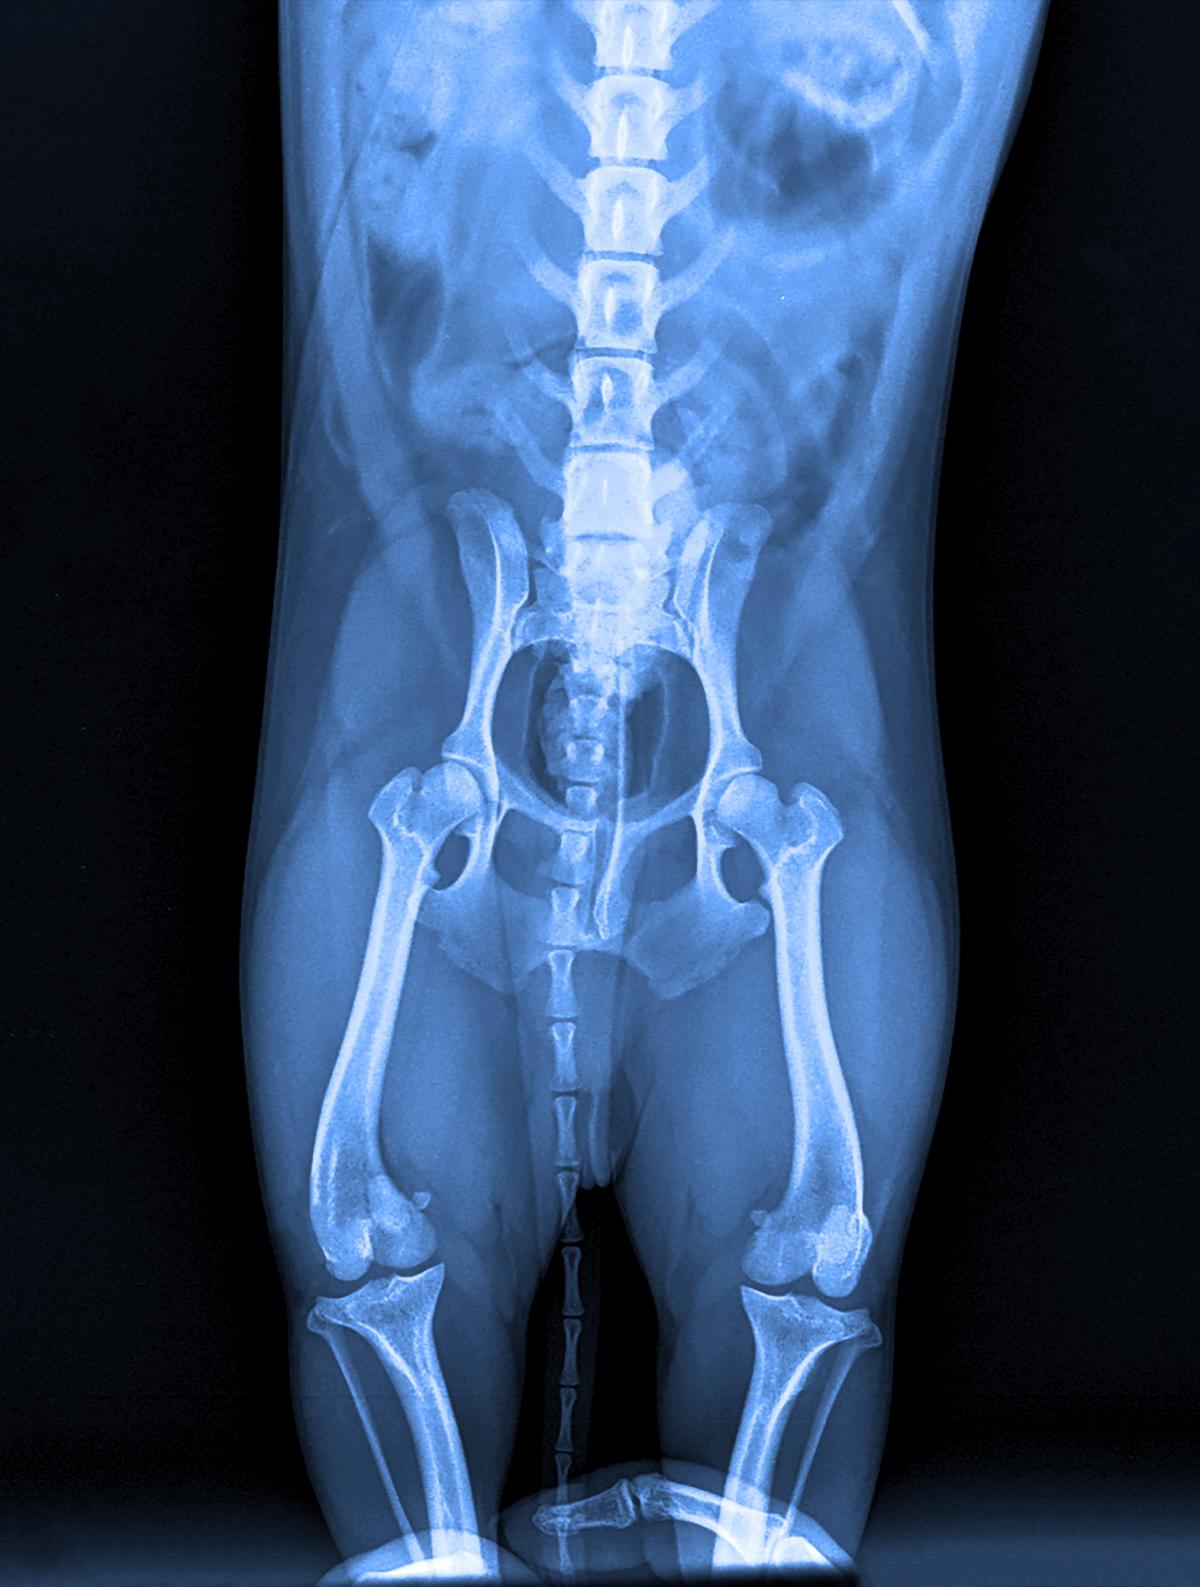

Unter einer Hüftdysplasie (HD) oder einer Ellbogendysplasie (ED) versteht man eine Erkrankung der Hüftgelenke beim Hund, welche meist erblich bedingt ist. Das Wort "Dysplasie" ist griechisch und bedeutet "schlechte Form". Leider kommt diese Erkrankung - vor allem bei größeren Hunderassen - häufig vor.

Erste Anzeichen einer Hüftdysplasie können sich zum Beispiel durch Bewegungsunlust, Lahmheit, einem breitbeinigen Gang oder Druckschmerz zeigen. Das Ausmaß der Symptome bzw. Beschwerden variiert je nach Alter, und Etwicklungsstadium der Krankheit. In schweren Fällen kann sich auch eine Arthrose entwickeln, weshalb eine tierärztliche Diagnose und Behandlung entscheiden ist.